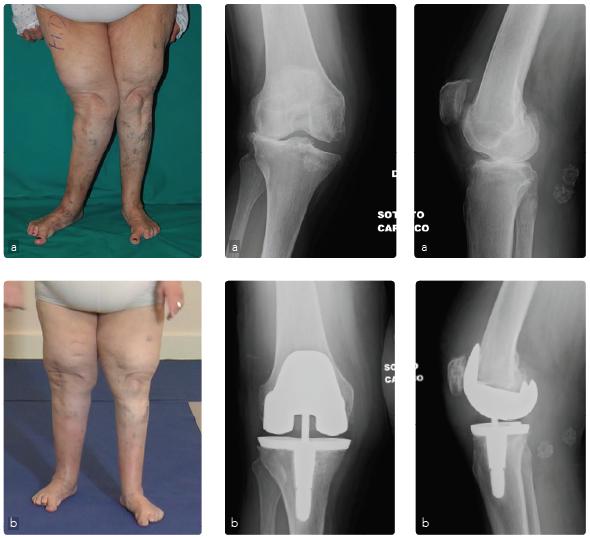

Caso 1: Protesi di ginocchio in grave valgismo

Femmina, 54 anni, affetta da gonalgia cronica in ginocchio valgo artrosico (valgismo >30°) (a). La deformità e l'artrosi comportavano una grave impotenza funzionale e dolore con deambulazione consentita per brevi tratti con l'ausilio di un bastone. Il trattamento chirurgico è consistito nella correzione dell'asse del ginocchio e una sostituzione protesica con protesi parzialmente vincolata (b). La paziente in seguito all'intervento è tornata a deambulare senzo bisogno dell'ausilio di bastoni, ed a salire e scendere autonomamente le scale.